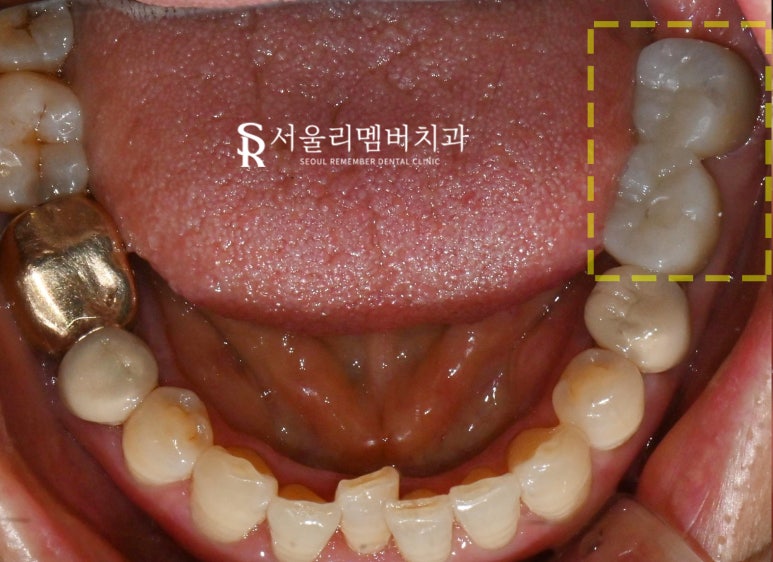

내원 당시 사진과 개선 후의 사진을

비교하면 큰 변화를 확인할 수 있습니다.